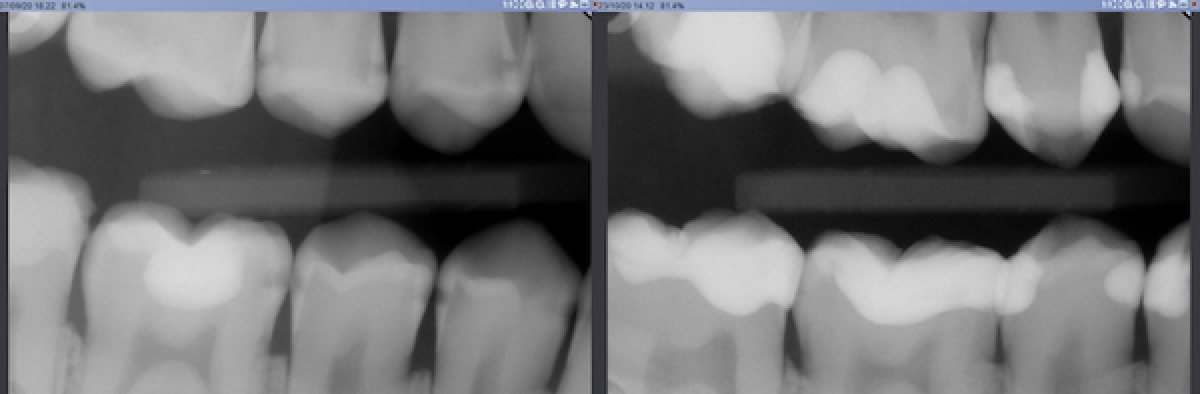

Baseline and post op bitewing rx (Fig.16)